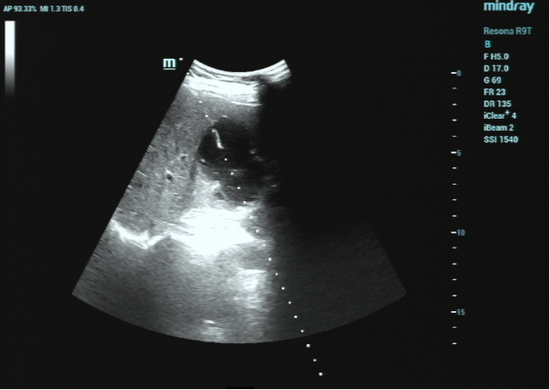

1. 精准定位: 超声就像医生的“透视眼”。在治疗前,超声仪器会清晰地显示囊肿的大小、位置,以及与周围大血管、脏器的关系,规划出最安全的进针路线。

2. 细针穿刺: 局部麻醉后,医生用一根很细的穿刺针(比平时打针的针头粗不了多少),在超声的实时监控下,精准地刺入囊肿中心。

整个治疗在超声设备的实时引导下进行,医生可以清晰看到穿刺针的路径,避开重要的血管和神经,从而在精准治疗的同时,进一步降低并发症风险。